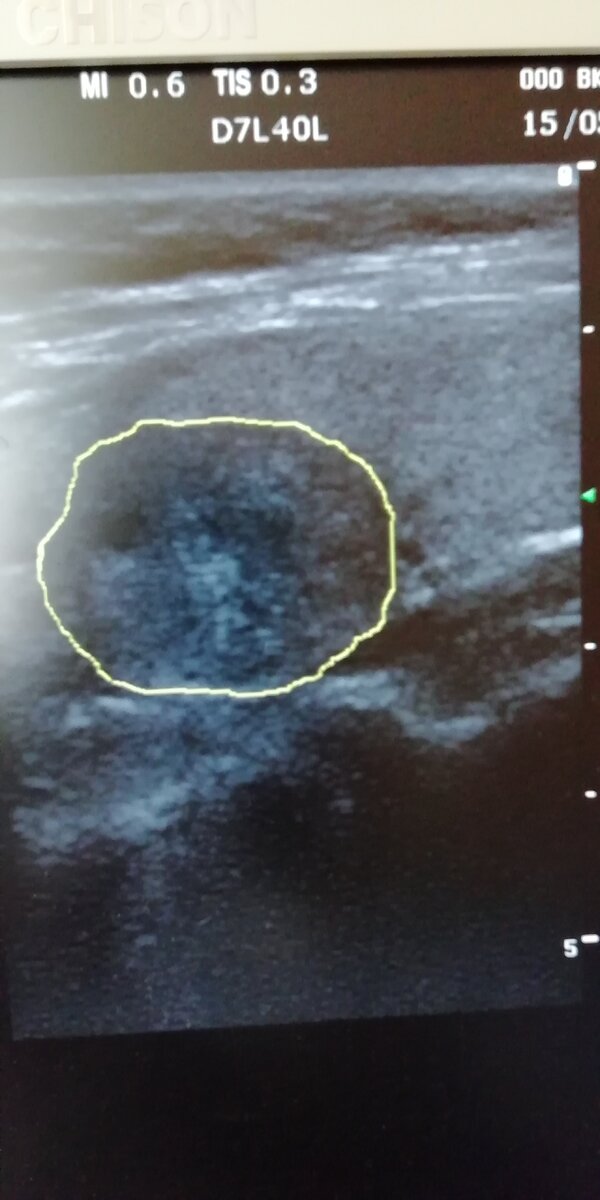

так выглядит крупный узел в правой доле щитовидной железы. фото автора.

Проблемы с щитовидной железой можно достоверно выявить всего двумя способами. Первый - узи. Оценивается увеличение объема, наличие узлов и активность кровотока. В норме объем щитовидки у женщин до 18 см3, плюс минус кубический сантиметр. У мужчин - до 25 см3. В среднем же объем колеблется между 10 и 15 кубиков. Скорость кровотока в норме до 25 см. сек. Если выше - есть резон заподозрить активность процесса. В организме всегда так - повышенный кровоток говорит о наличии активной работы. В статье о фиброзно-кистозной мастопатии я уже немного писал на тему: если в узле активный кровоток, есть повод заподозрить его злокачественность.

В щитовидке - это не всегда рак, но повышение активности - абсолютно точно. Узлы и доброкачественные, и злокачественные выглядят абсолютно одинаково. На глаз их отличить нельзя! Только пункция - прокалывание иголочкой под контролем узи с забором материала на гистологический анализ.